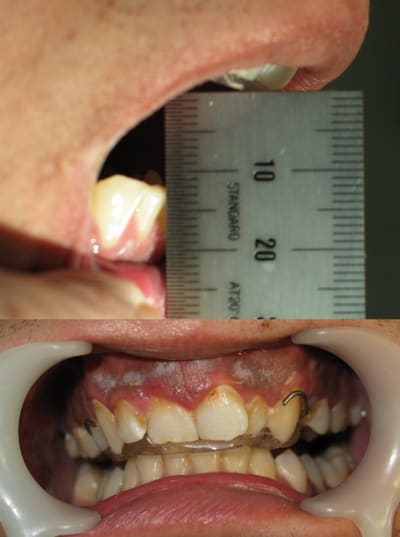

Cela progresse dans le bon sens, mais c'est très lent pour la récupération.

As-tu déjà transformé en Prothèse Occlusale sur la photo?

Pourrais-tu envoyer une photo des points de contact actuels sur ton plan?

Les miens sont nettement plus "plan" dans le sens frontal.

tu te fiches de nous Occlusion c'est la même photo que J+1, tu appelles ca de la progression?

15 jours que ton patient est dans le même état...

20 % & ouverture 3,5 cm